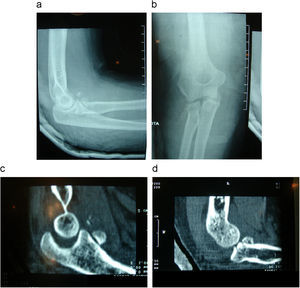

Regan y Morrey20 distinguieron tres tipo de fractura: el tipo i son fracturas menores del 10% de la coronoides, es importante destacar que no se producen por mecanismo de avulsión, ya que la cápsula articular se inserta más distal, a 5–6mm de la punta21; se producen por mecanismo de cizallamiento, por lo que son un signo patognomónico de un episodio de inestabilidad (subluxación o luxación)5. El tipo ii son aquellas fracturas que afectan entre el 10 y el 50% de la coronoides, y el tipo iii son fracturas con afectación de más del 50%. Ring y Jupiter22 también han destacado la importancia de las fracturas de pequeño tamaño por asociarse a mecanismo lesional posterolateral; se las considera las más problemáticas. Estos autores observaron en su serie de tríadas malignas fracturas de la coronoides de pequeño tamaño (<50%) con apariencia de pequeños fragmentos triangulares, en la radiografía lateral del codo, difíciles de distinguir de las fracturas de la cabeza del radio (fig. 2). Su apariencia es diferente a la de las fracturas más grandes que se asocian a las fracturas-luxación del olécranon.

Recientemente, O’Driscoll et al23 han propuesto una nueva clasificación basada en el reconocimiento de fracturas de la faceta anteromedial de la coronoides. La localización y la morfología de la fractura se relacionan con unos determinados patrones globales de la lesión del codo. Las fracturas tipo i son fracturas de la punta; incluyen un subtipo i con un tamaño inferior a 2mm, y un subtipo ii con tamaño mayor a 2mm. Las fracturas tipo ii son las fracturas que afectan a la faceta anteromedial de la coronoides (fig. 3); se distinguen 3 subtipos: el subtipo i son las fracturas del reborde anteromedial, el subtipo ii son las fracturas que afectan tanto al reborde anteromedial como a la punta, y el subtipo iii son aquellas en que se fracturan el reborde anteromedial, la punta y el tubérculo sublime. Es importante distinguir las fracturas que afectan a la faceta anteromedial de la coronoides, pues se deben a mecanismo lesional distinto al posterolateral. Las lesiones asociadas y el tratamiento, por tanto, también serán específicos. Tienen lugar por un mecanismo de rotación posteromedial en varo y carga axial, y asocian subluxación en varo. Raramente asocian fractura de la cabeza radial o lesiones ligamentosas mediales; sin embargo, sí asocian la lesión del ligamento humerocubital lateral. Cuando hay luxación de codo ambos ligamentos están lesionados. La radiología convencional es con frecuencia insuficiente para el estudio de este tipo de lesión, por lo que la TC tiene un papel fundamental en su evaluación. Las fracturas anteromediales de la coronoides aisladas no son típicas de las tríadas. En cambio, podemos encontrar fracturas combinadas de la faceta anteromedial y de la base de la coronoides en casos de lesiones posterolaterales (tríadas).